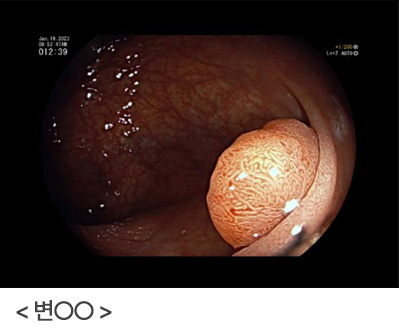

남자와 폐경 후 여성분들에게 나타나는 빈혈은 위장관의 악성질환에서 조금씩 피가 나는 것이 원인일수 있기 때문에, 반드시 위, 대장내시경을 시행하여 위암이나 대장암이 있는지 확인이 필요합니다. 만성질환에 동반된 빈혈은 환자분이 적응하면서 어지러운 증상을 호소하지 않기 때문에, 불편감을 못 느낄수도 있으나 그냥 지나치지 말고 반드시 내시경검사를 통하여 확인할 필요가 있다는 것을 다시 한번 깨달은 증례였습니다.